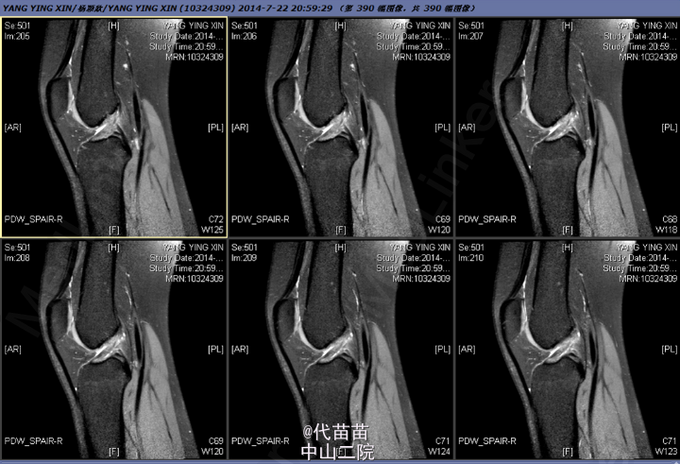

患者女,27岁,因扭伤后右膝关节不适2月余入院。

右膝关节麦氏征(+),蹲走试验(-),过伸试验(-),过屈试验(-),浮髌征(-),髌骨加压研磨试验(-),前抽屉试验(+),后抽屉试验(-),侧方应力试验(-),lachman征(+),关节活动度0-135度,股四头肌无明显萎缩,肌力正常;肢端血运、感觉、活动正常。

诊断: 1.右膝关节前交叉韧带损伤;2.右膝关节半月板损伤 行右膝关节镜检,前交叉韧带重建,内侧半月板修补术